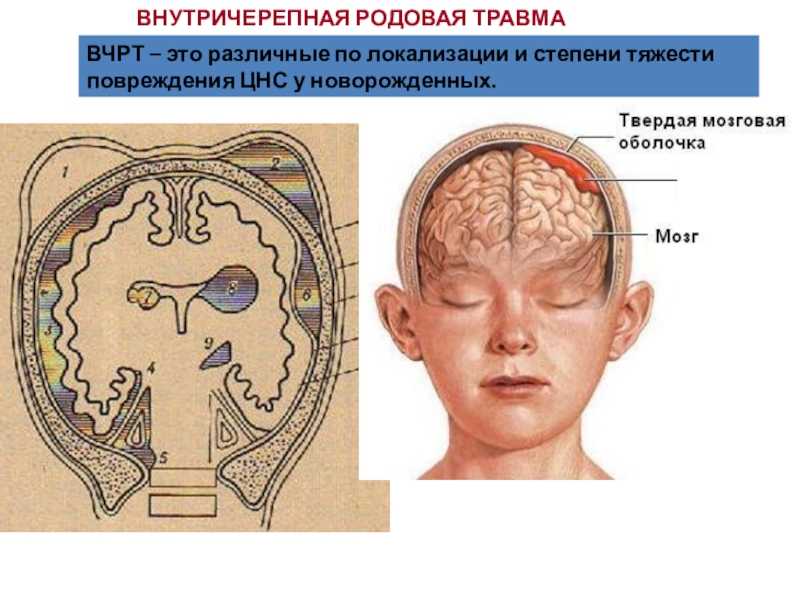

Внутричерепные кровоизлияния у новорожденных презентация - 92 фото